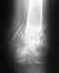

Смещение после закрытой репозиции переломов обеих лучевых костей со смещением + перелома шиловидного отростка на правой руке. Допустимое смещение, или нужно делать открытую репозицию?

Уважаемые специалисты, прошу Вашего экспертного мнения.28.08.2020 после неудачного приземления получил травму обеих рук.29.08.2020 обратился в ближайший травмпункт, по результатам рентгена - перелом обеих лучевых костей со смещением + перелом шиловидного отростка на правой руке.Выполнена закрытая репозиция.Наложен гипс (чуть ниже локтя).03.09.2020 контрольный рентген.Врач, который же и делал репозицию - сказал, есть небольшое смещение, но идеально совместить осколки все равно не получится. Смещение допустимое, ничего страшного.Сказал приходить через месяц.Гипс оставил тот же самый.Сейчас самочувствие хорошее, даже вот могу немного печатать на клавиатуре. Только при разгибании больших пальцев есть дискомфорт и боль, и при усилии нажатия (напр. когда надо вилку вставить в розетку). Сустав стараюсь не крутить.Однако начитавшись про последствия неправильного сростания костей, меня терзают сомнения.По-вашему, всё нормально и можно спокойно долечиваться в гипсе, операция не нужна?Какие могут быть долговременные последствия такого смещения?Рентген от 03.09.2020 (5 дней после репозиции) прилагаю:https://drive.google.com/drive/folders/1isOdNQyIx0iE-neLqHW7Ddx1X2zg1MjQ?usp=sharingБольшое спасибо за Ваше доброе дело, долгих лет Вам.

Есть небольшое смещение. По возможности лучше бы его устранить, иначе может быть небольшой дефицит сгибания в лучезапястном суставе.